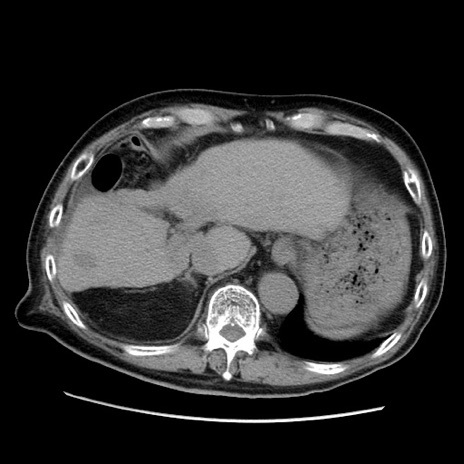

症例21(横断像)

【症例】70歳代男性

【主訴】腹痛

【現病歴】肝硬変・肝細胞癌にてかかりつけの方。約9時間前に食後より腹痛出現。症状が徐々に増悪し、嘔吐出現したため来院。

【既往歴】肝硬変、肝細胞癌(RFA、TACE後)

【身体所見】意識清明、表情苦悶様、BT 36℃、BP 129/78mmHg、P 88bpm、SpO2 97%(RA)、右上腹部から心窩部にかけて圧痛あり、反跳痛なし、筋性防御あり。

【データ】WBC 5800、CRP 0.16